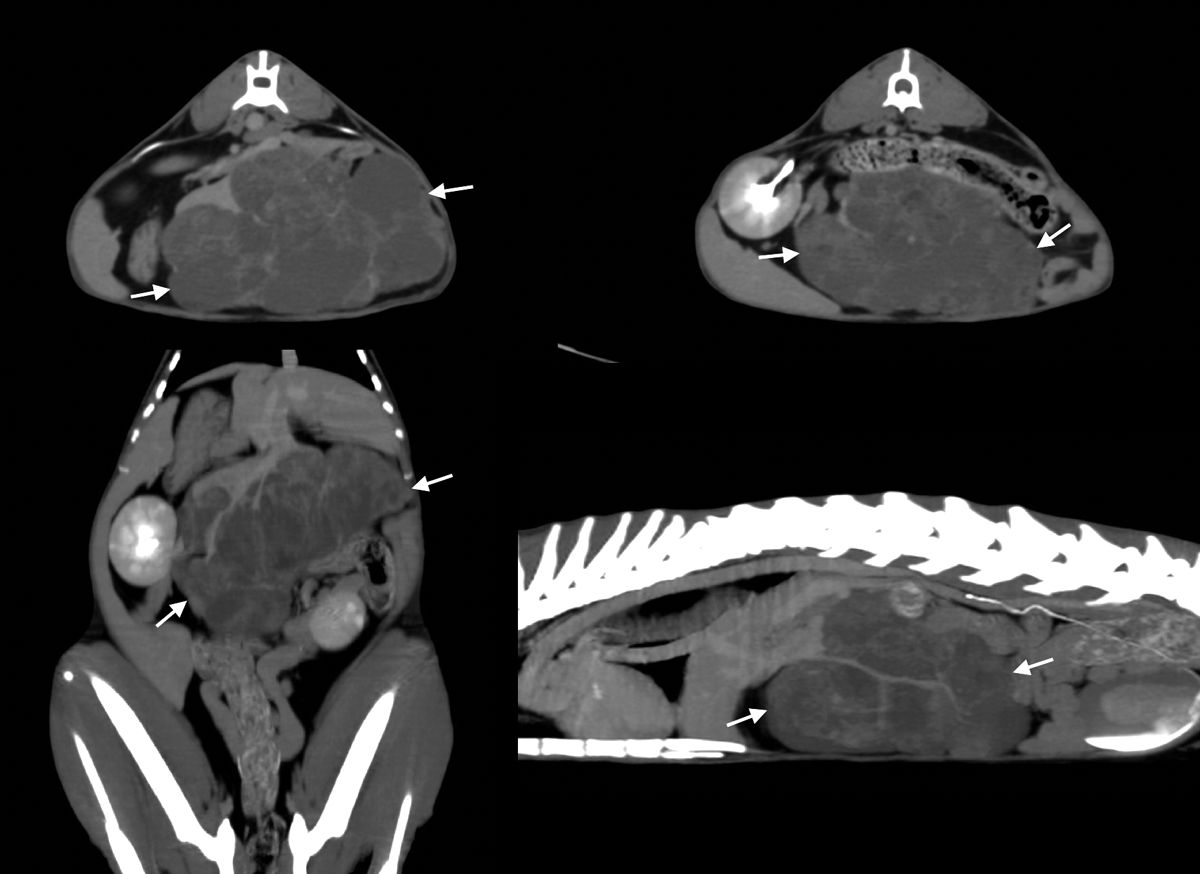

Imagini CT ale unei tumori hepatice la o pisică. Imagini transversale (sus) și imagini reformatate în plan dorsal și sagital în proiecție de intensitate maximă (jos). Se poate observa o formațiune de mari dimensiuni în partea centrală a ficatului (săgeți), cu contururi clar delimitate, ceea ce facilitează excizia chirurgicală.

Figura 5. Imagini CT ale unei tumori hepatice la o pisică. Imagini transversale (sus) și imagini reformatate n plan dorsal și sagital n proiecție de intensitate maximă (jos). Se poate observa o formațiune de mari dimensiuni n partea centrală a ficatului (săgeți), cu contururi clar delimitate, ceea ce facilitează excizia chirurgicală. Laurent Blond

Imagistica CT necesită anestezierea generală a pacientului, urmată de administrarea intravenoasă a unei substanțe de contrast iodate. Această metodă este foarte utilă pentru investigarea imagistică a întregului ficat, în special la câinii de talie mare, la care ecografia ar putea avea limitări. Câinii pot fi așezați în decubit dorsal sau ventral, iar imaginile obținute în plan transversal pot fi transpuse în planuri diferite. Ficatul va prezenta, de obicei, o atenuare omogenă a țesuturilor moi. Investigațiile CT sunt recomandate în special pentru a evalua localizarea exactă și posibila diseminare a maselor hepatice atunci când se ia în considerare intervenția chirurgicală (Figura 5). Metoda CT este de asemenea foarte utilă în evaluarea anomaliilor vasculare, în special a anastomoze portosistemice (intra- sau extrahepatice); în aceste cazuri, sunt necesari trei timpi de achiziție după administrarea substanței de contrast, în timpul fazei arteriale, porte și celei venoase sistemice [2].